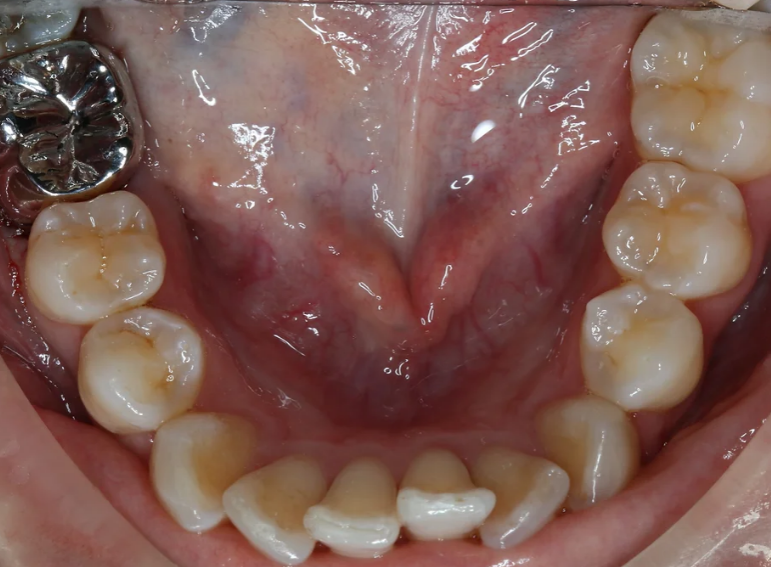

Root fillings, whitening and repair of two fractured incisors.

Root canal treatment and combined internal and external whitening.